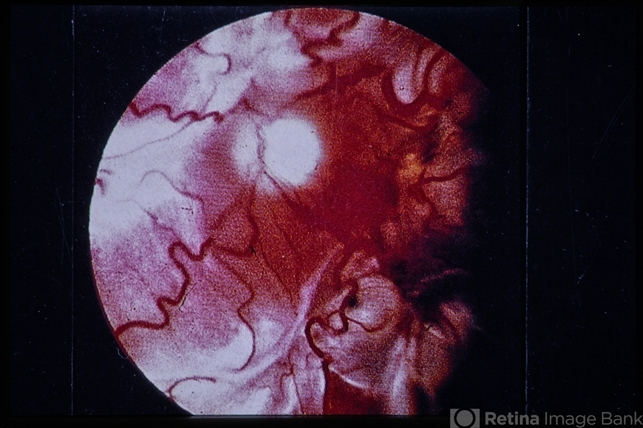

- Massive Vitreous Retraction

- Massive vitreous retraction.